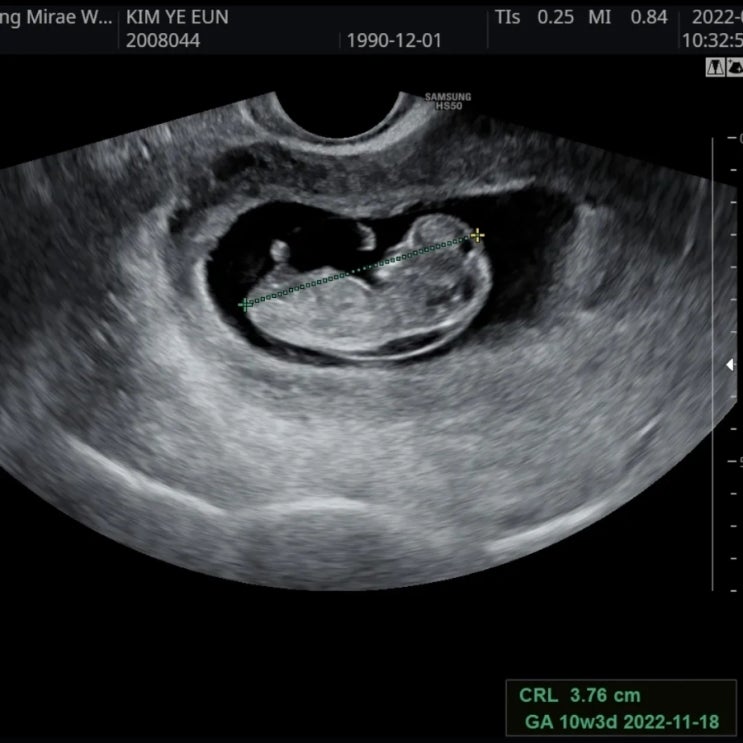

#34. (13주2일차) 정밀초음파 다시 보고 옴, 코뼈랑 목투명대 측정

안녕하세용~~ 제 이름은 이뿌리애오. 어제 뿌리 초음파를 다시 보러 병원에 갔다. 지난주에 NIPT랑 정...